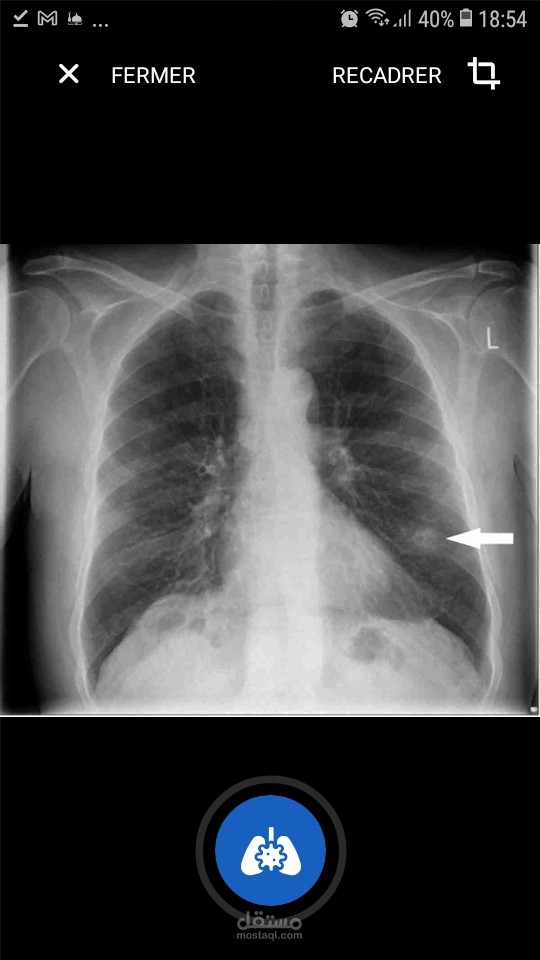

Neuron Chest X Ray Classifier هو تطبيق محمول (android) يساعد أخصائي الأشعة على قراءة أشعة الصدر بشكل أسرع وأكثر دقة من أي وقت مضى.

تستخدم تقنية الذكاء الاصطناعي للتنبؤ بالأمراض من صورة الأشعة السينية على الصدر